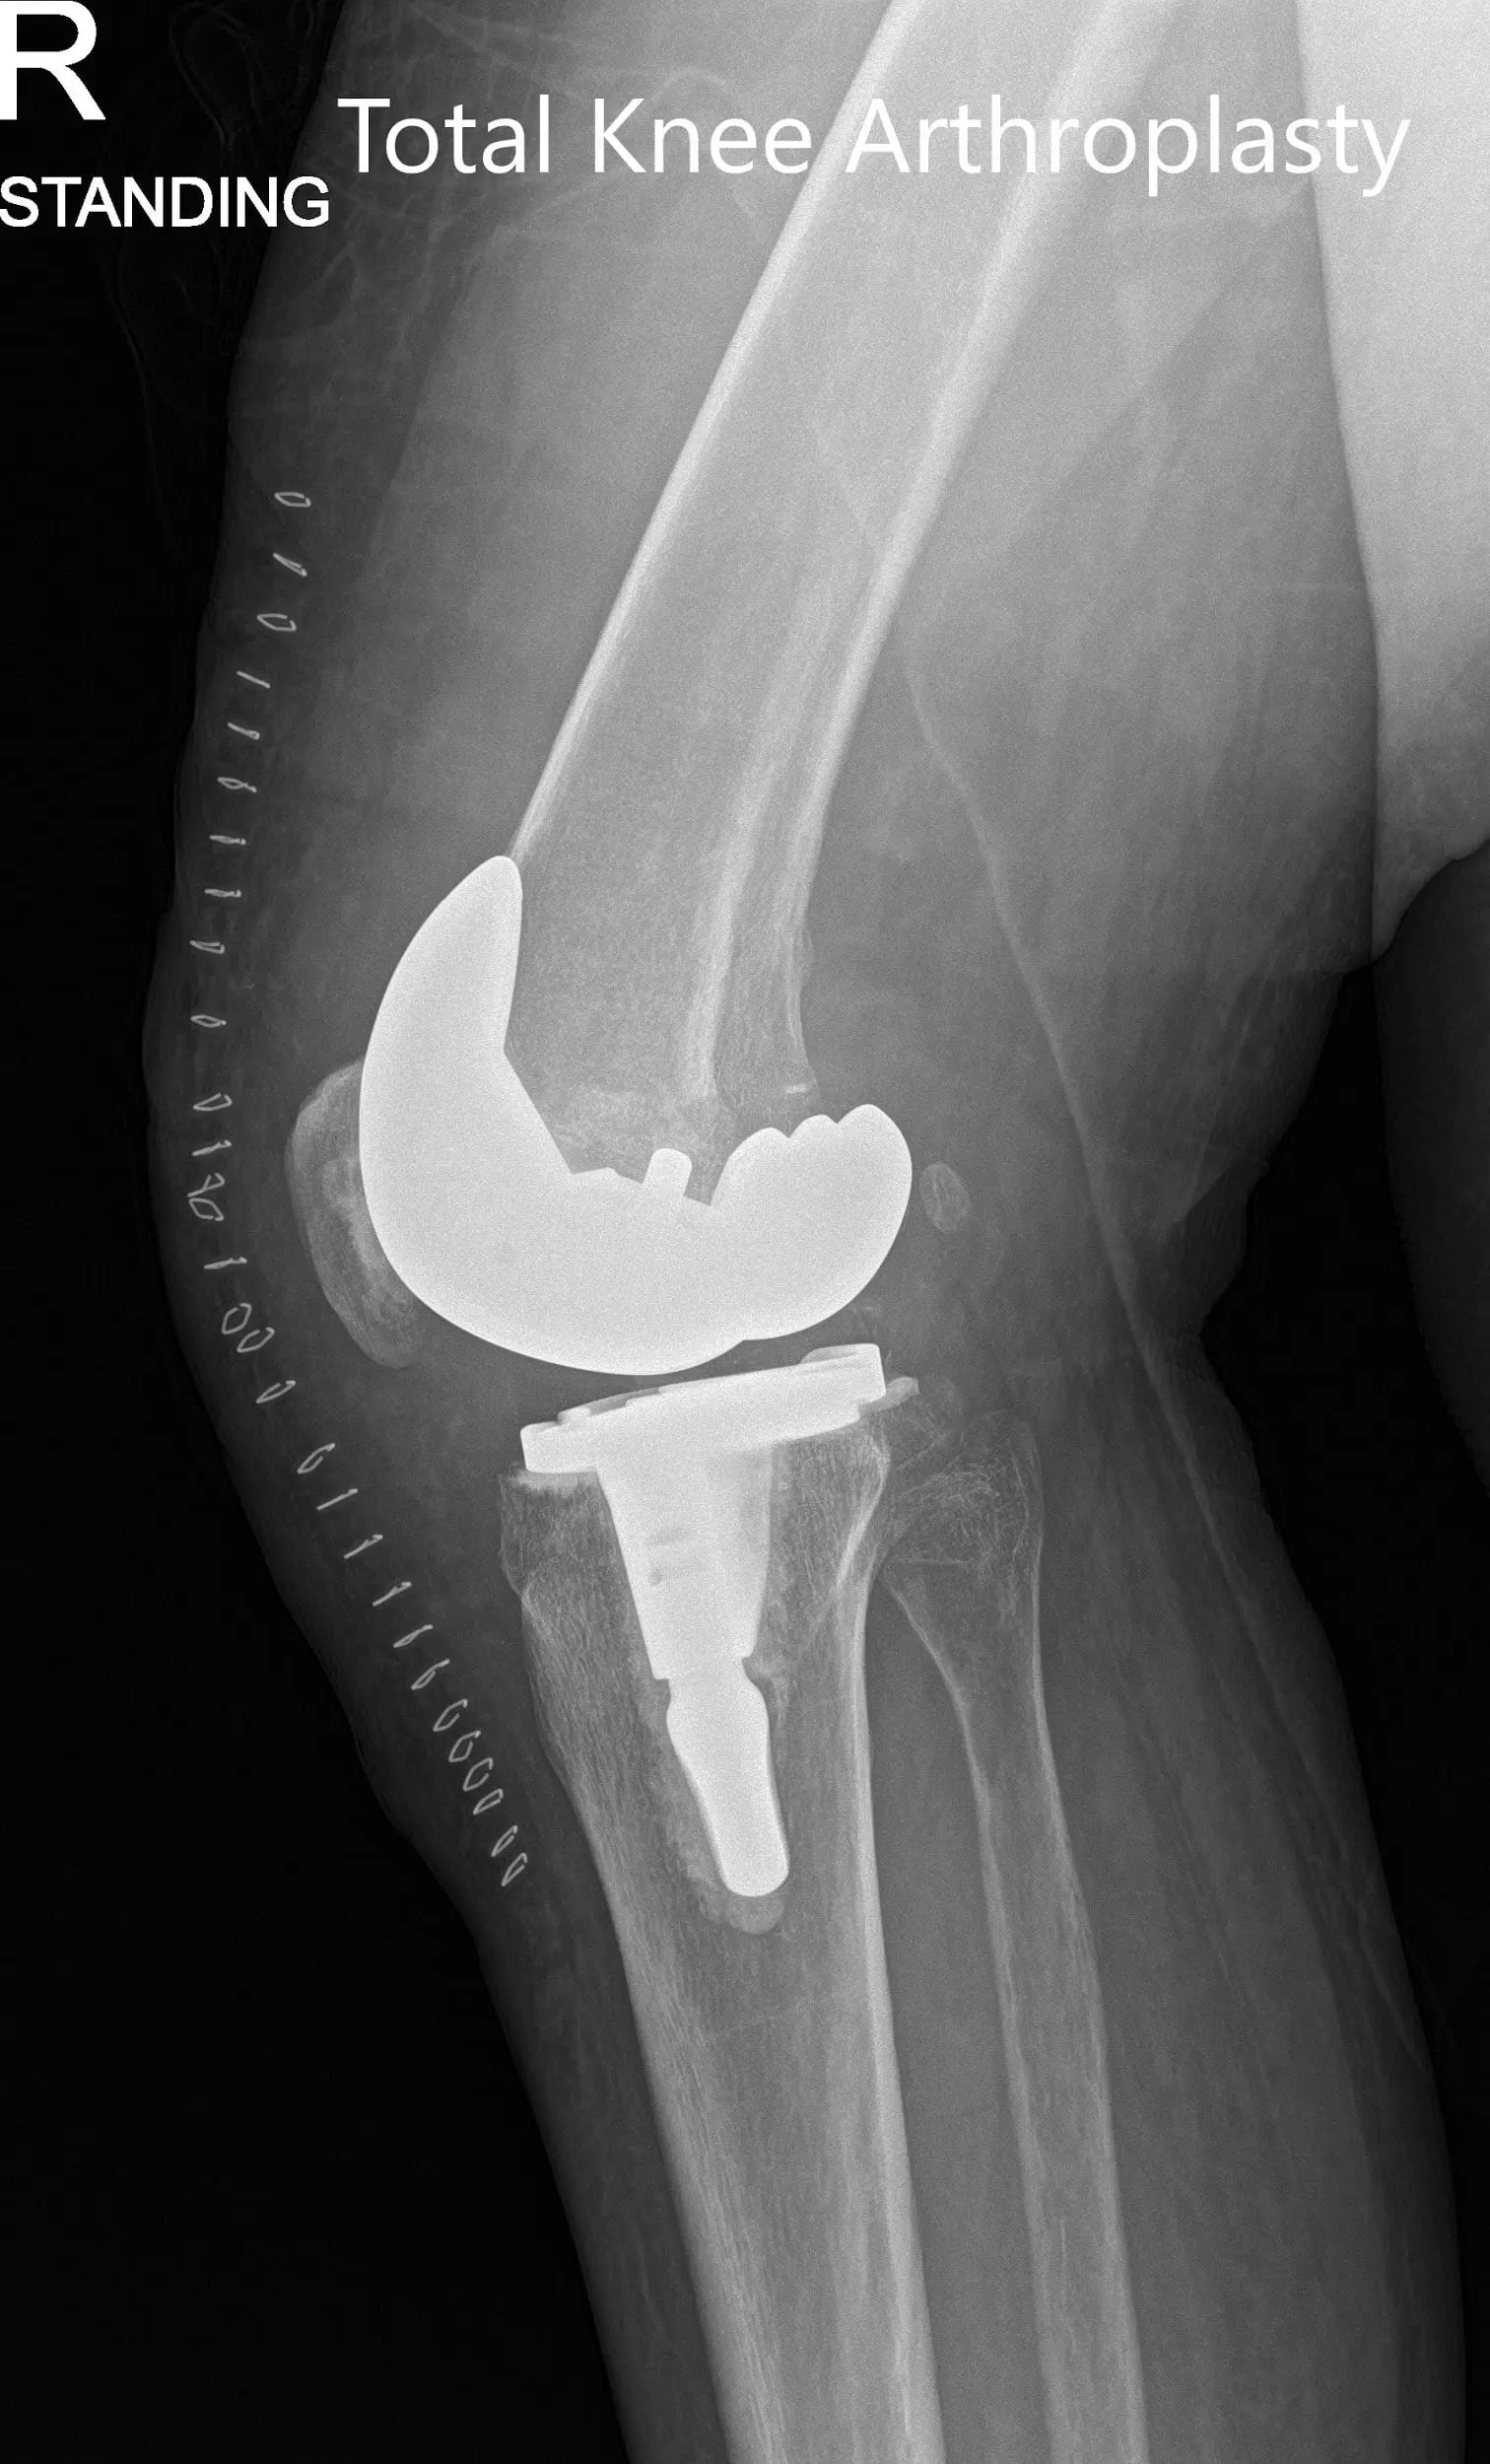

Postoperative x-ray showing the anteroposterior and lateral views of the right knee

Postoperative x-ray showing the anteroposterior and lateral views of the right knee - img 2

Postoperative x-ray showing the anteroposterior and lateral views of the right knee.

IMPLANTS USED: Tibia stemmed size E with a stem extension with highly cross-linked polyethylene patella 35 mm with femur size 11 with 10-mm posterior stabilized polyethylene.